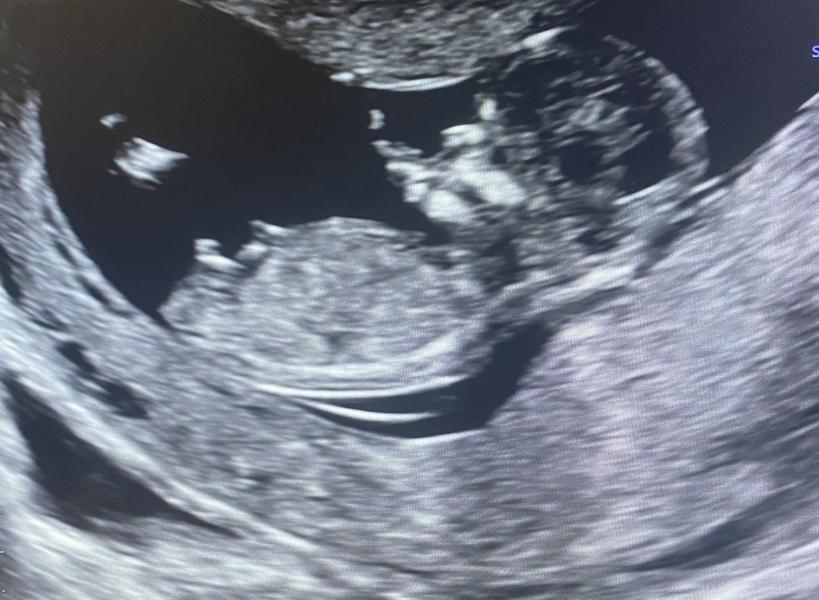

Мальчик или девочка? Сказали 99% мальчик

Тут так даже и не разберешь по фото, такой ракурс у вас на узи 🧐даже и предположить сложно 50/50. А на узи сказали похоже на мальчика? Мне как-то прям так увеличили этот бугорок, что и сомнения нет в мальчике 🤷🏽♀️

Может я что-то не понимаю, но половые признаки же развиваются к 16 неделям. Как в 12 вам могут говорить 99%. В 12 недель там половой бугорок